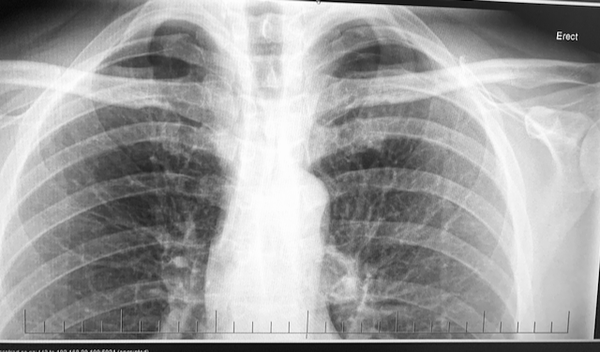

respiratory

NZ COPD 2025 guidelines. Key Recommendations for pharmacological management of COPD.

BTS 2023 guidelines on pleural disease. Key points.